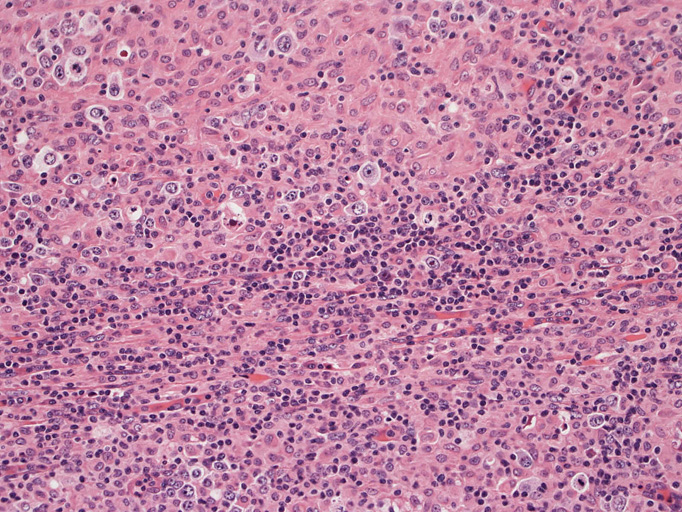

結節構造内では, 好酸性細胞質をもつ組織球の増生を背景に大型異型細胞が散在性または集蔟して増殖している。被膜下にも線維化組織内にbizzarreな大型細胞が認められる。リンパ球は小型リンパ球が大型異型細胞を含む組織球性の結節辺縁に存在する。大型細胞は, centroblastic cellが多く, その他 Hodgkin cell-like cell, RS細胞様巨細胞, 腎臓型の核をもった細胞, 多型核の細胞など多彩な形態を示す。異型核分裂像をふくむ核分裂像が多い。

大型異型細胞の形態